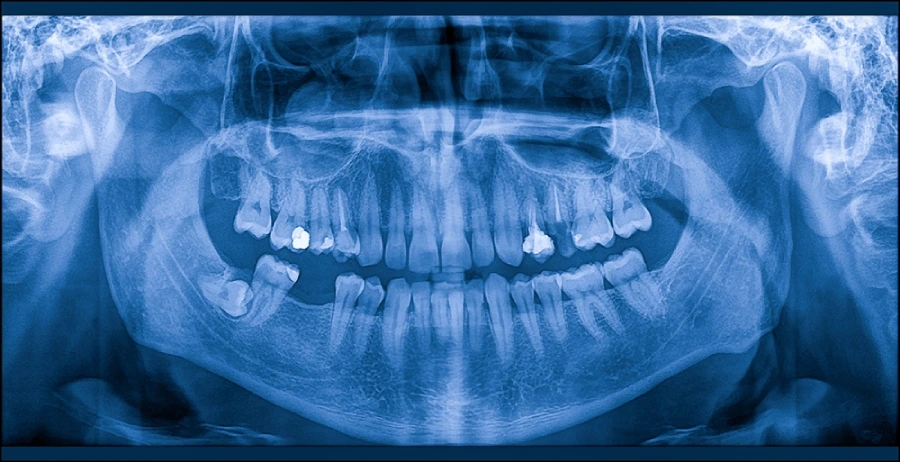

パノラマエックス線撮影

パノラマエックス線写真は、上下の歯や顎の骨、顎関節までを一枚で確認できるレントゲン検査です。

むし歯や歯周病の進行状況、親知らずの位置、顎の骨の状態などを総合的に把握でき、目に見えないトラブルの早期発見に役立ちます。

初診時や定期的な検査で撮影することで、お口全体を見据えた適切な治療計画を立てることができます。